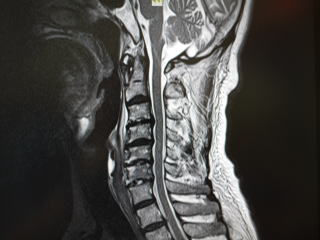

頚長筋 石灰化 (484 無料写真)

首の痛み西荻窪駅・久我山駅すぎなみ脳神経外科・しびれ・頭痛クリニック。

石灰沈着性頸長筋腱炎:急に痛くて首が回らない!つぐ脳神経外科・頭痛クリニック厚木市の脳神経外科即日MRI検査駐車場あり。

その首の痛みは寝違い?クリニックブログキジマ あたまのクリニック。

首の痛みをきたす疾患はこの7つすぎなみ脳神経外科・しびれ・頭痛クリニック西荻窪駅・久我山駅。